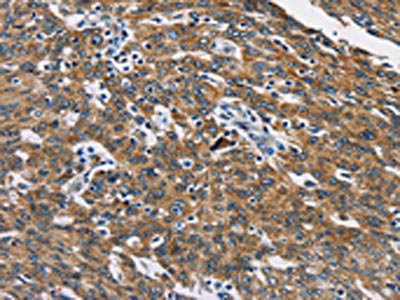

The image on the left is immunohistochemistry of paraffin-embedded Human ovarian cancer tissue using CSB-PA942303(CAT Antibody) at dilution 1/40, on the right is treated with fusion protein. (Original magnification: ×200)

The image on the left is immunohistochemistry of paraffin-embedded Human gastric cancer tissue using CSB-PA942303(CAT Antibody) at dilution 1/40, on the right is treated with fusion protein. (Original magnification: ×200)